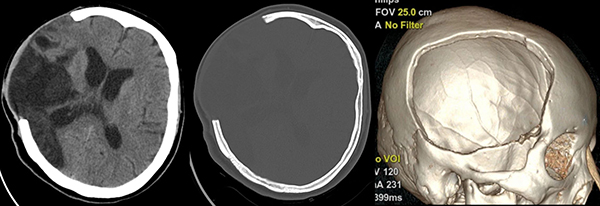

神经外科在接诊后,为患者完善头颅三维CT检查及钛网塑形,并为患者成功实施了颅骨修补成形术。术后10天拆除患者伤口缝线,头颅外形恢复了正常,无新发神经功能障碍,左侧肢体肌力进一步好转,为继续康复治疗创造了有利条件,目前已转院继续接受康复治疗。

▲术前头颅CT显示右侧额颞顶骨部分缺损